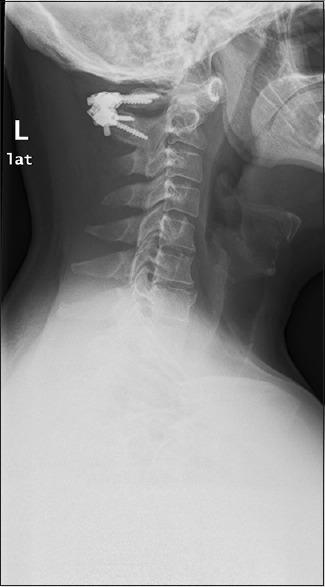

A 46-year-old male with symptomatic atlantoaxial instability secondary to os odontoideum underwent bilateral C1 and C2 translaminar screw/rod fixation as C1 lateral mass fixation was precluded by an anomalous vertebral artery. The follow-up evaluation 2½ years postoperatively revealed an asymptomatic patient without recurrent neck/shoulder pain or clinical signs of instability. To better assess the feasibility of utilizing this approach in the general population, we retrospectively analyzed 502 consecutive cervical CT scans performed over a 3-month period in patients aged over 18 years at a single institution. Measurements of C1 bicortical diameter, bilateral laminar length, height, and angulation were performed. Laminar and screw dimensions were compared to assess instrumentation feasibility.

一名46岁男性,因齿突骨导致有症状的寰枢椎不稳,由于椎动脉异常而无法进行C1侧块固定,遂接受了双侧C1和C2经椎板螺钉/棒固定。术后2年半的随访评估显示患者无症状,无复发性颈部/肩部疼痛或不稳定的临床体征。为了更好地评估在一般人群中使用这种方法的可行性,我们回顾性分析了在一家机构对18岁以上患者在3个月内连续进行的502例颈椎CT扫描。测量了C1双皮质直径、双侧椎板长度、高度和角度。比较椎板和螺钉尺寸以评估器械置入的可行性。